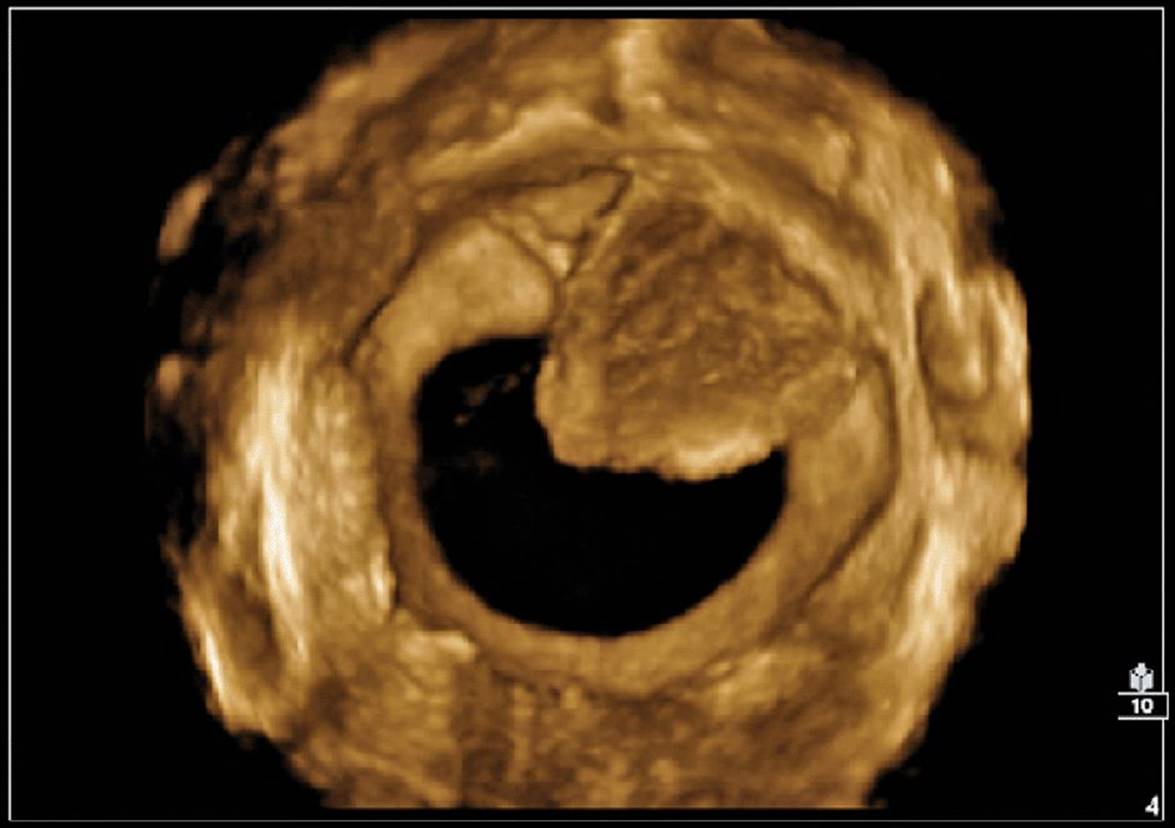

Three-dimensional sonography has many clinical applications in gynecologic disorders (Figs. 8–28 through 8–37). As in obstetrical 3D, gynecologic 3D affords depiction of the uterus and ovaries in any selectable scan plane, including those not readily obtained with 2D. These include improved depiction of endometrial masses such as polyps or submucosal fibroids, improved localization and calculation of changes in fibroid volume, enhanced depiction of tubal masses, intrauterine device localization, and uterine malformations. Three-dimensional depiction of tumor morphology and vascularity within ovarian masses has important implications in distinguishing benign from malignant masses.

Because of its ability to display in the coronal plane, 3D sonography is accurate in depicting intraluminal masses such as polyps or fibroids. The location of an intrauterine contraceptive device (IUCD) within the endometrium is readily depicted with 3D sonography. Three-dimensional sonography obtained in the transverse plane of the uterus fundus is also useful in identifying tubal masses since their origins can be traced to the cornual area of the uterus.